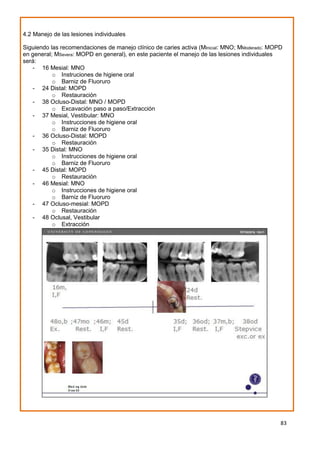

2.4.2 Manejo individual de lesiones

El plan de manejo individual de lesiones de caries está hecho a la medida de cada lesión.

El diagnóstico de caries con ICCMSTM

(Tabla 6) se puede aplicar en las decisiones de

manejo de caries. El nivel de intervención depende de la clasificación clínica de caries de

la superficie o diente y de la extensión radiográfica (cuando esta información está

disponible) de la lesión en esmalte o dentina. Los niveles de manejo clínico

recomendados para lesiones activas se definen de la siguiente manera:

MInicial Estadío de manejo inicial de caries (Manejo No Operatorio (MNO) - control)

MModerada: Estadío de manejo moderado de caries (en general MOPD)

MSevera: Estadío de manejo severo de caries (en general MOPD)

Para superficies sanas y lesiones detenidas, se recomienda la prevención basada en el

Con base en la mejor evidencia disponible (ver Apéndice H) y dependiendo de la

categoría de caries, ICCMSTM

recomienda las actividades que se muestran en la Tabla 8

para dentición permanente y en la Tabla 9 para dentición primaria, discriminando según el

tipo de superficie (Ver Apéndice H para nueva evidencia para intervención de lesiones

Las recomendaciones de manejo para caries coronal en dentición permanente son las siguientes:

Surperficie

Estadío

ICCMS™

Fosas y fisuras Mesial-distal (proximal)

Superficies

lisas

MSano Prevención basada en riesgo (Consulte la sección anterior)